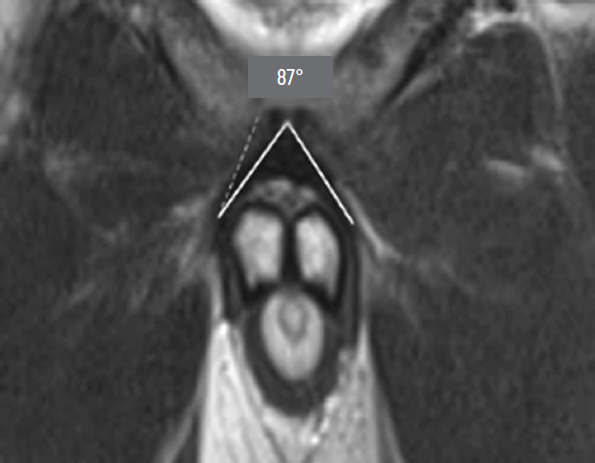

During preoperative assessment, penile length was recorded in both the flaccid and stretched states (median: 6.75 cm and 12 cm, respectively). Penile length in erection was measured by the patient at home (median: 12.5 cm). All patients underwent pelvic magnetic resonance imaging (MRI) to assess the topographic anatomy of the penile suspensory apparatus preoperatively. The following parameters were recorded: length and width of the suspensory ligament (median: 2.7 cm and 1.4 cm, respectively), thickness of the subcutaneous fat layer (median: 2.85 cm), angle of ligament divergence in the frontal plane (median: 65.8°), and the angle between the corpora cavernosa and the pubic symphysis (median: 17.42°) (Fig. 1–Fig. 5).

Fig. 5. Angle between the corpora cavernosa and the pubic symphysis.